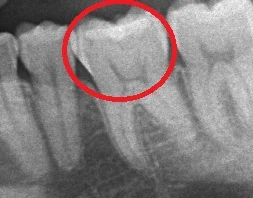

で、こちらがレントゲン像です。

パッと見ではそこまで大きな虫歯には見えません。

ただ、本人も言っていましたが、神経が上の方に大分伸びているタイプですので、下手に放置しすぎると神経の治療になりかねない状況です。